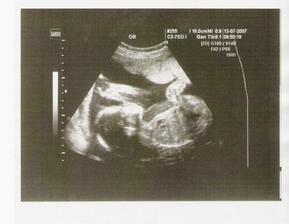

Letos k nám asi přiletí Ježíšek o měsíc dřív :o). 24.11.2007 máme termín porodu a já přivedu na svět druhého potomka. Pravděpodobně to bude zase chlapeček a bude se jmenovat Kubík. Tomík (jeho budoucí velký bráška) se už na něj moc těší a my samozřejmě také. Pomalu už začínáme vše připravovat a nakupovat.